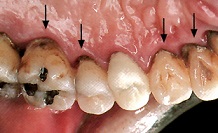

歯周病がなかなか治らない原因、それは、歯肉縁下歯石にあります。右の写真の矢印の所にある

黒い色の部分です。プラークが血液と結びついて石灰化してつくられます。歯周病菌を多量に含む

病原性の高い歯石です。歯石の周囲から、毒素を放出するので歯肉の炎症やを起こしたり、歯を支える

骨をとかします。歯肉縁下歯石は、固く除去しにくいです。なので、少しずつ取り除いていきます。